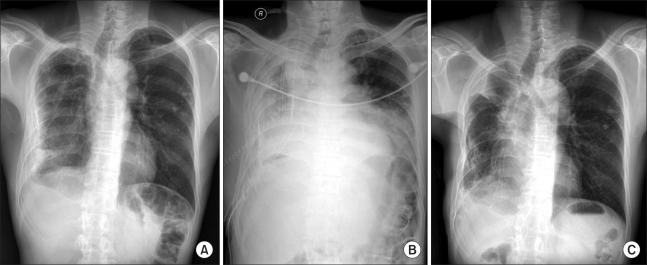

A surgically treated case of chronic necrotizing aspergillosis with pleural invasion.

Aspergillus is a ubiquitous fungus and can cause many levels of disease severity. Chronic necrotizing aspergillosis is a rare disease and few cases have been reported in Korea. We experienced a case of pleural aspergillosis that was treated successfully with medical and surgical interventions. The 52-year-old man who was diagnosed with chronic necrotizing pulmonary aspergillosis underwent surgical treatment including a lobectomy, decortication, and myoplasty. The patient was also medically treated with amphotericin B followed by voriconazole. Pleural irrigation with amphotericin B was also performed. A multi-dimensional approach should be considered for treating chronic necrotizing pulmonary aspergillosis.